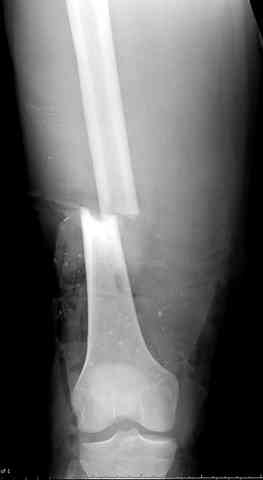

После пары Irrigation& Debridment с вакуумом можно провести окончательную фиксацию интрамедуллярным методом. Чем быстрее, тем лучше, потому что сроки нахождения наружных фиксаторов на конечности тоже имеют значение, риск осложнения увеличивается после длительного пребывания наружного фиксатора.

Открытые переломы, если имеется хороший доступ из раны можно сопоставить и зафиксировать первично пластиной, потому что несопоставленные переломы намного труднее репонируется в поздние сроки. Активизация больного за счет стабилизации кости благоприятно влияет на сращение, а также облегчается манипуляция по закрытию дефекта.

Необходимо доказать проникновение инфекции в кость, иначе агрессивные сегментарные остеотомии кости удлиняет процесс восстановления.

Показания к применению мышечно-ротационной пластики на голени являются обнаженный фрагмент кости, мышца, прикрывая кость восстанавливает питание, а снаружи мышца служит ложем для кожной пластики.

здесь случай с политравмой, перелом зафиксирован наружным фиксатором, после третьей irrigation&debridment фиксация бедра пластиной с последующей кожной пластикой.

Djoldas Kuldjanov, MD